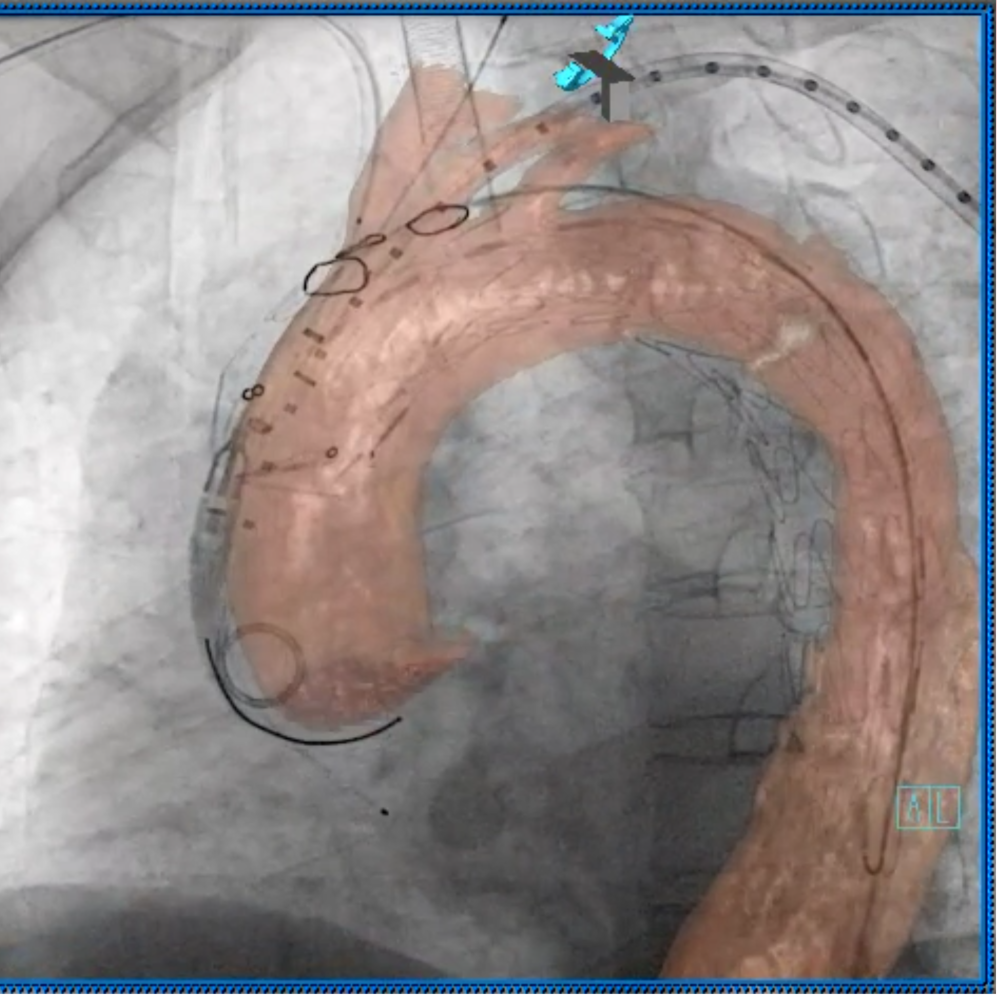

3D影像融合

术中3D影像引导,主体支架精准定位

3D影像引导下,

主体支架窗口与弓上三分支开口对位

依次超选无名、左颈总及左锁骨下动脉